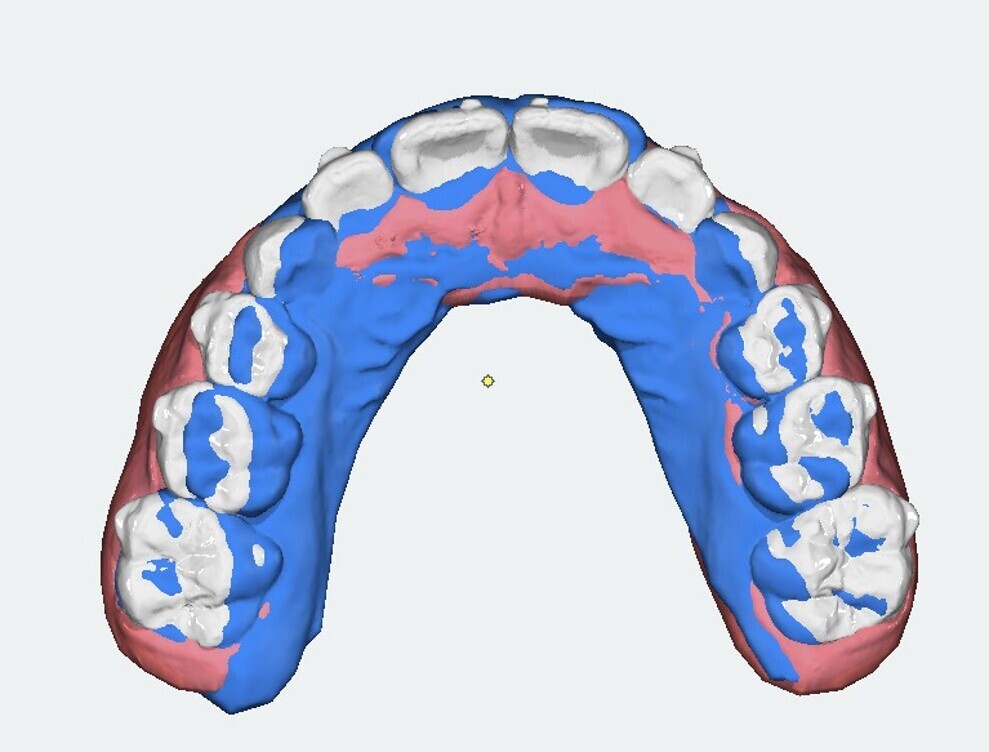

Analysis of the models in Autodesk Netfabb software (Fig. 12) showed regularisation of the arches and an increase in the maxillary inter-canine diameter of 2.61 mm and in the maxillary intermolar diameter of 2.29 mm. The superimposition of the arches at T0 and T1 (Fig. 13), performed using OnyxCeph3 (Image Instruments), was very significant and showed the shift from the initial arch shape and size to a wider shape posteriorly but with significant control of the maxillary incisor area.

Fig. 13: OnyxCeph3 superimposition. Blue = initial arch shape and size.